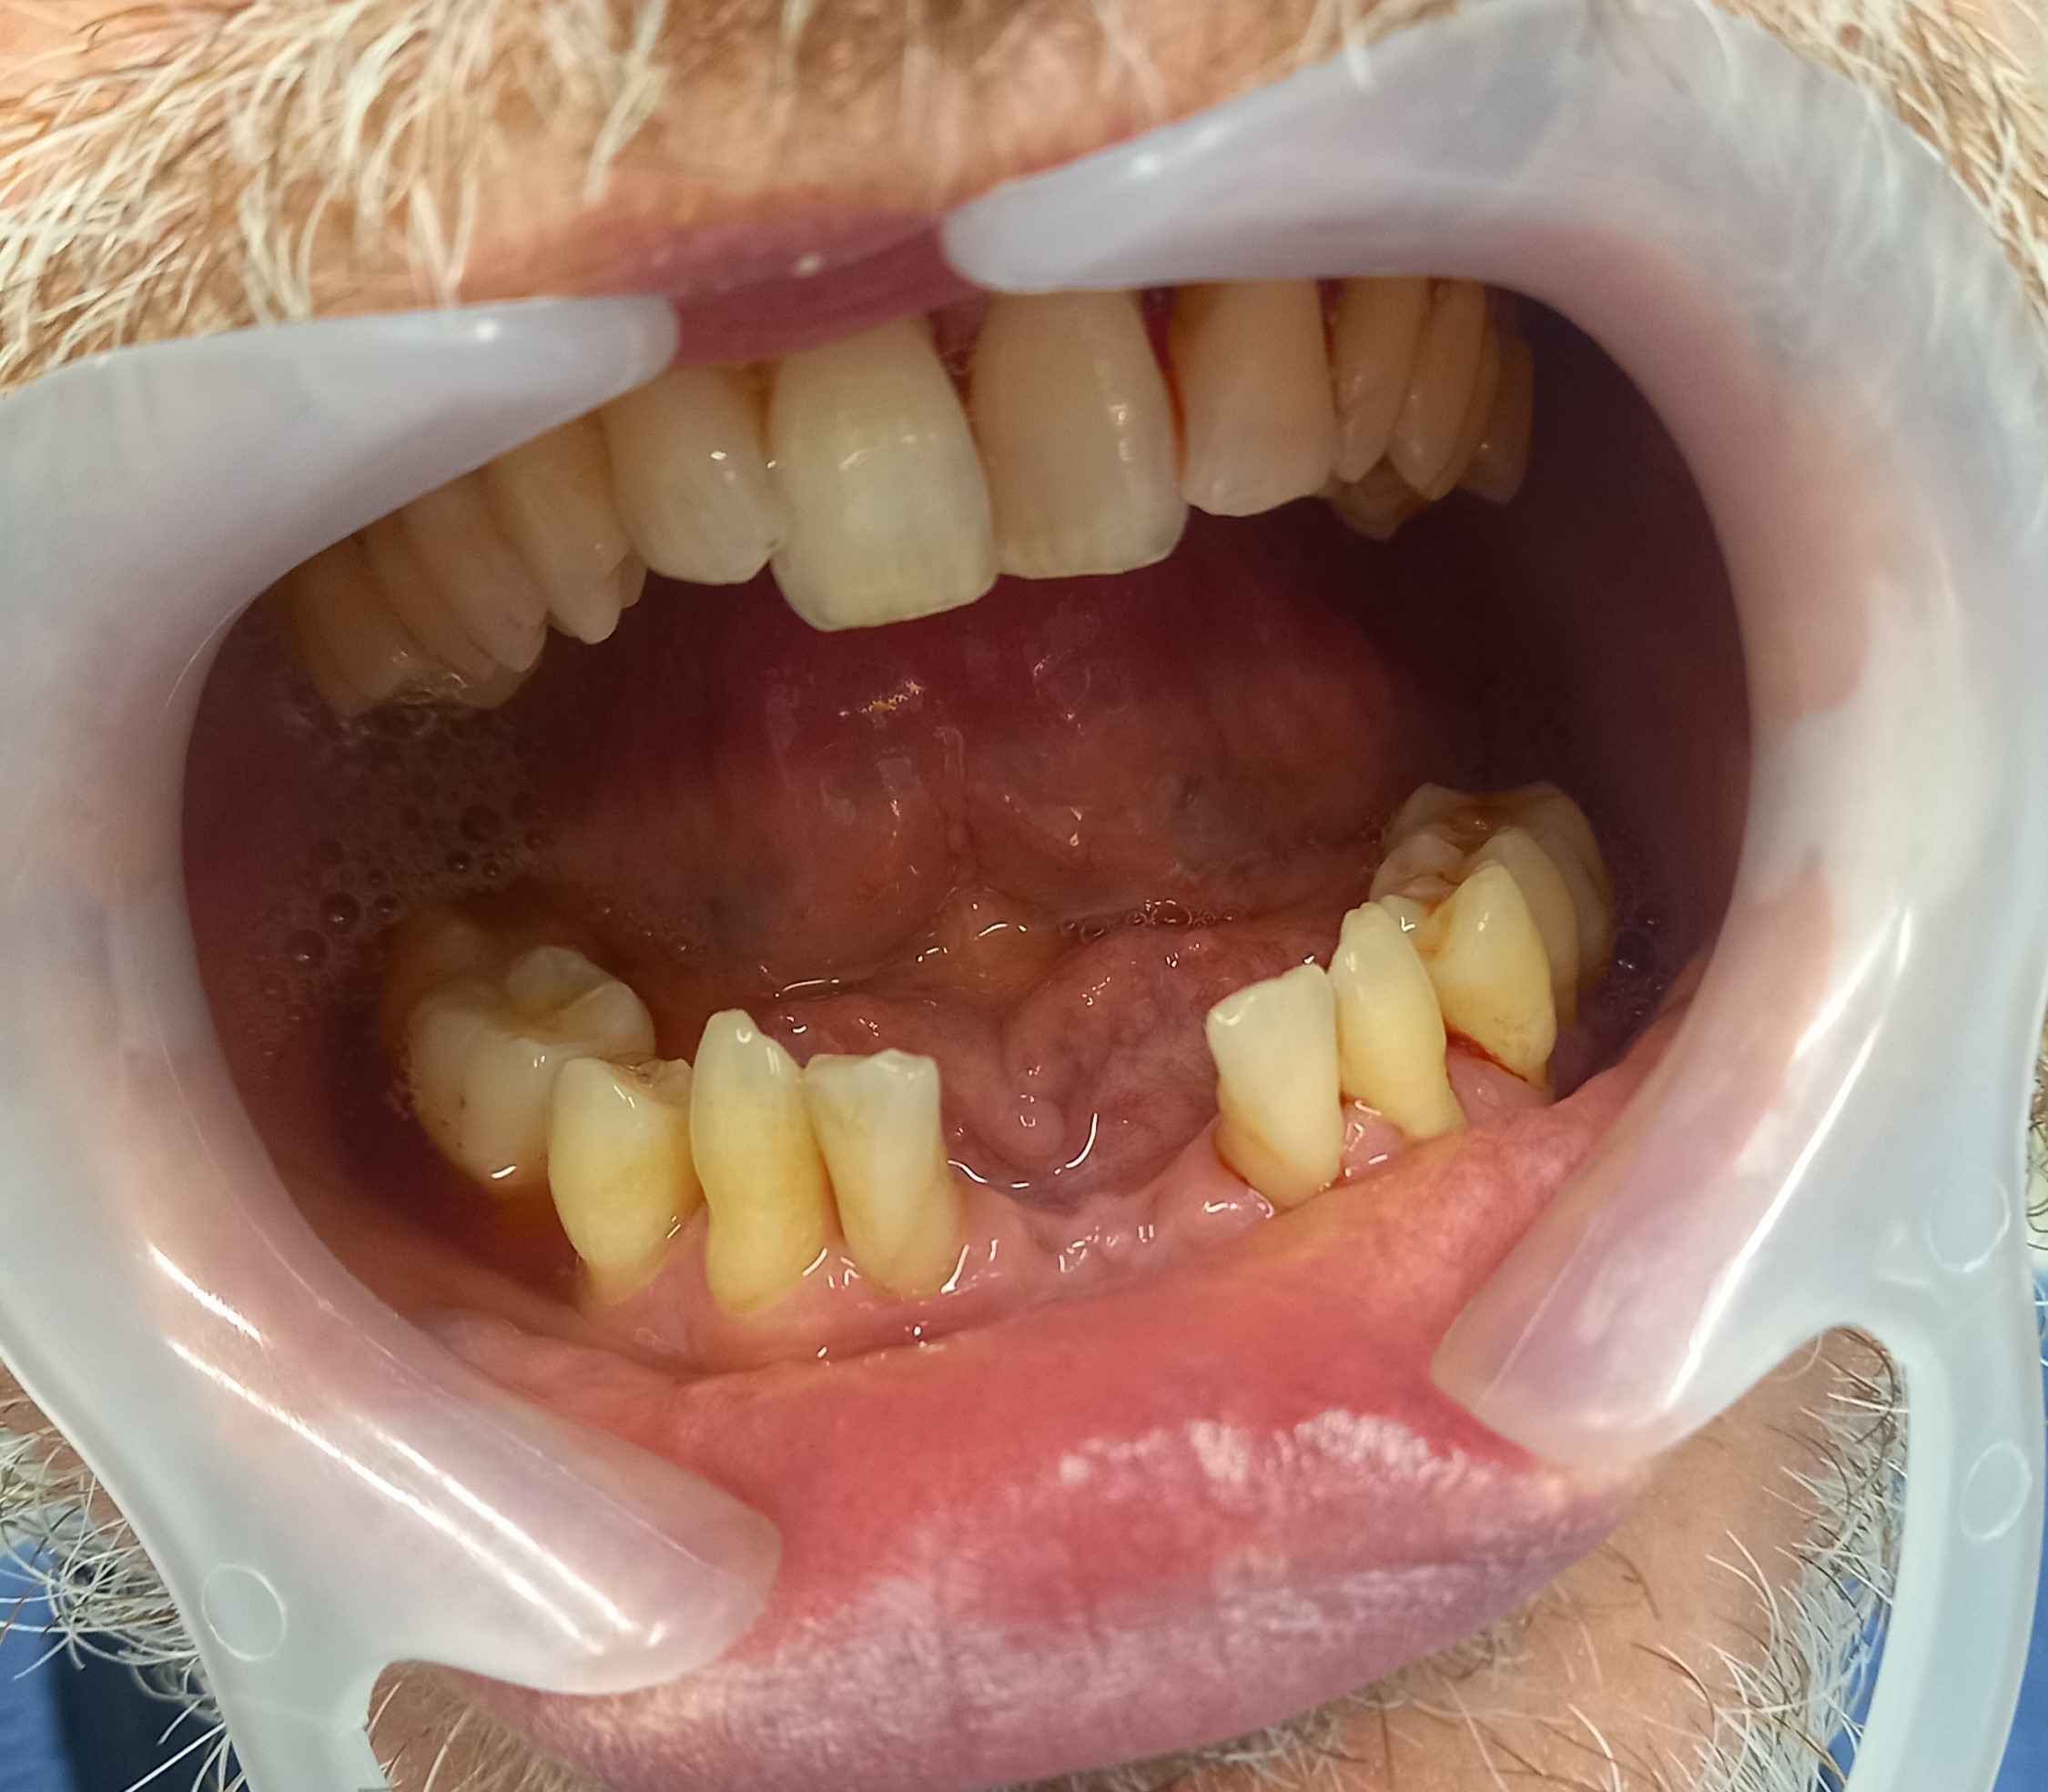

Ο ασθενής είχε για χρόνια μία πρόσθια νωδότητα στην κάτω γνάθο, την οποία αποφάσισε να αντικαταστήσει με προσθετική εργασία γιατί δεν αγαπούσε τα εμφυτεύματα. Μετά τις απαραίτητες εργασίες λήφθηκαν αποτυπώματα και κατασκευάστηκε ολοκεραμική γέφυρα, η οποία κάλυψε άριστα τόσο λειτουργικά όσο και αισθητικά το προϋπάρχον κενό.

Ο ασθενής είναι πολύ χαρούμενος με τα νέα του δόντια.

ΠΡΙΝ

ΜΕΤΑ